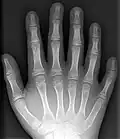

Röntgenfoto van hand met 6 vingers